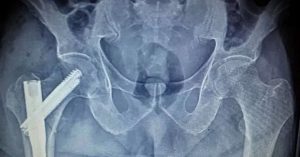

Cerrahi yöntemler en sık tercih edilen yaklaşımdır. Total veya parsiyel kalça protezi, kırığın yerine ve kemiğin durumuna göre seçilir. Vida ile fiksasyon, özellikle femur boynu ve intertrokanterik kırıklarda uygulanır. Cerrahi, hastanın kısa sürede ayağa kalkmasını sağlar. Uzun süre yatakta kalmanın getirdiği pıhtı ve kas erimesi riski azalır.